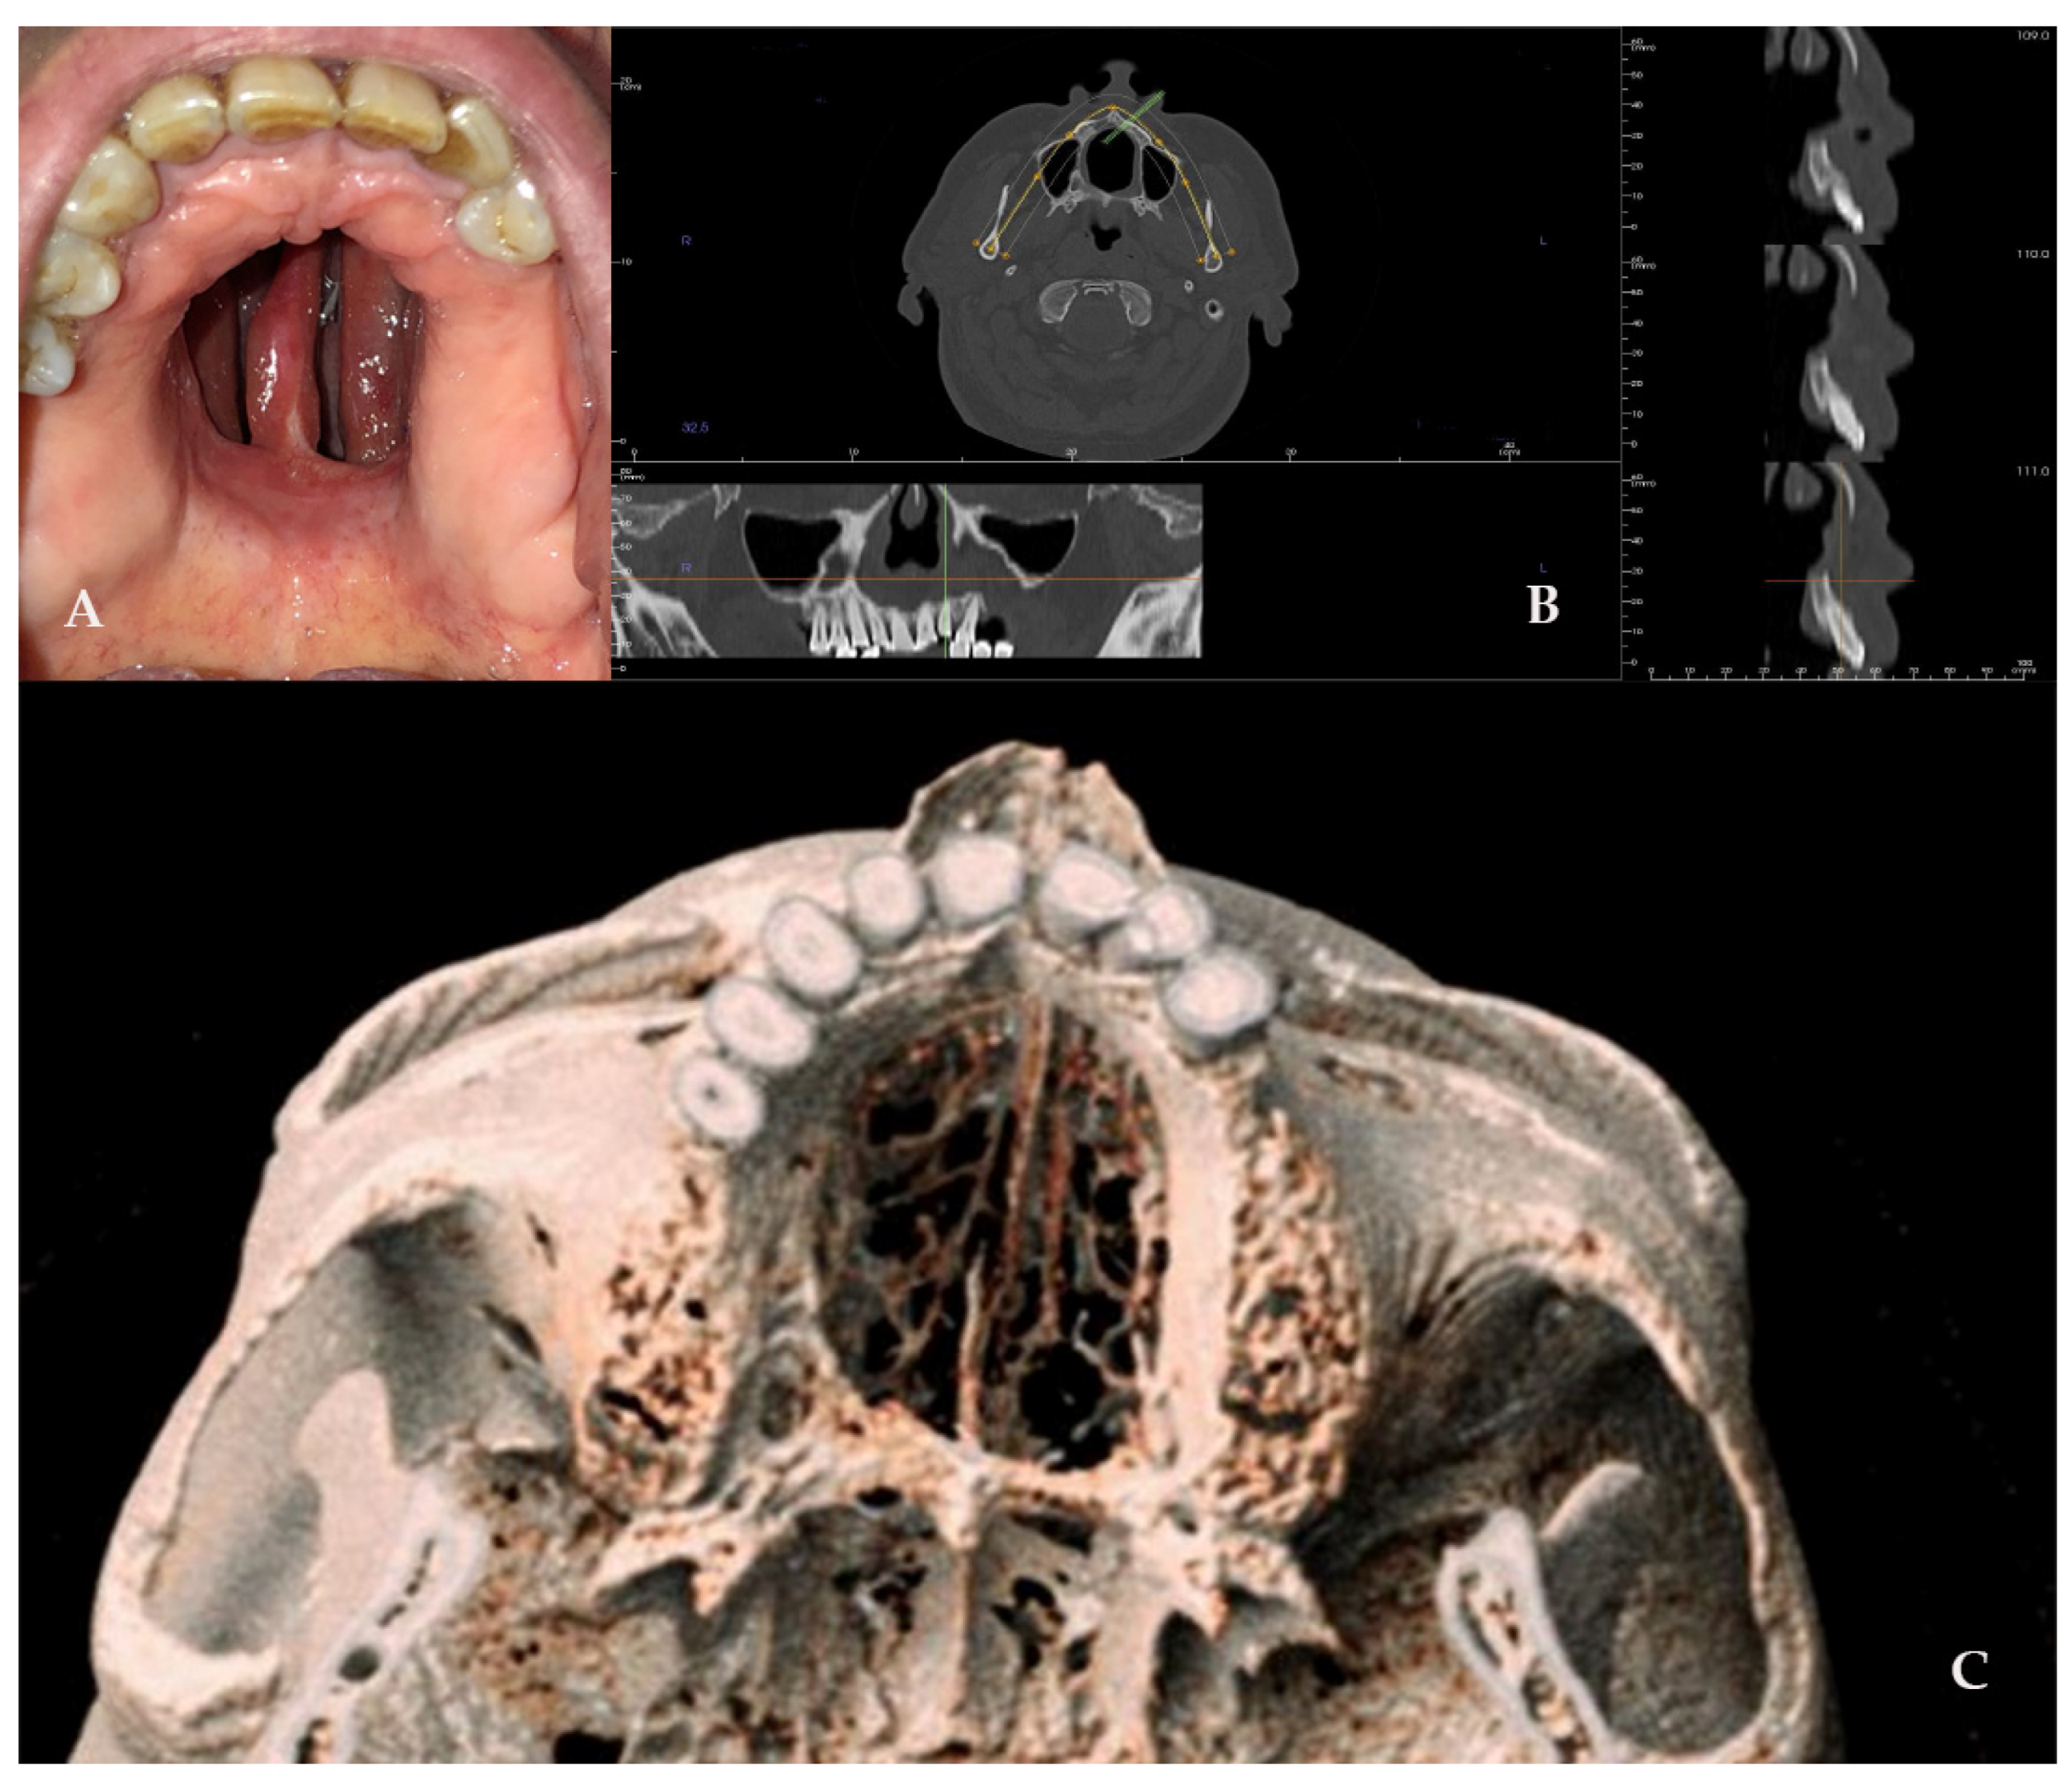

A 40-year-old female patient came to our attention in 2022, presenting a palatal/oro-nasal fistula measuring 2 cm in diameter along the major axis, with atrophic and burned soft tissues surrounding the lesion (Ia according to the Okay et al. classification [14]), as well as the loss of the right orbital floor and the eye. The patient was surgically treated to remove the inflamed and necrotic bone in another center, with the reconstruction of the orbital floor using a mesh. A wide bony and cartilaginous septal destruction with communication of the nasal cavity and collapse of the nasal pyramid was also shown at the clinical examination. Speech disturbances, rhinolalia, and eating difficulties were shown. In 2023, the patient underwent surgical intervention to reconstruct the palate. Under general anesthesia, the surgery was performed, starting with a Le Fort I osteotomy preceded by preplating to achieve the correct repositioning of the fragment. A careful dissection of the nasal and palatal mucosa was performed after the down fracture. A temporalis muscle rotation flap was harvested on the right side. The operation lasted three hours in the oro-tracheal tube. A nasogastric tube was placed and kept in place for seven days with standard antibiotic and anti-inflammatory therapy. The patient was discharged after four days.

The patient attended follow-up appointments at 1 week, 1 month, 6 months, and 1 year, with complete resolution of the fistula, improved speech capacity, and no difficulties with eating (Figure 7).

Figure 7. (AE) Radiographic and 3D reconstruction using InVivo6® and Anatomage Table EDU vers.8® (Santa Clara, CA, USA) software. DICOM files were imported in InVivo® (California, USA) software to obtain the axial, cross, and panorex sections. Afterwards, the DICOM files were imported into Anatomage Table® (Santa Clara, CA, USA) to obtain the 3D rendering. (F) Clinical presentation of the oro-nasal communication. (GJ) Radiographic and 3D reconstructions using InVivo6® and Anatomage Table EDU vers.8® (Santa Clara, CA, USA) software at the one-year follow-up. (K) One-year clinical follow-up.